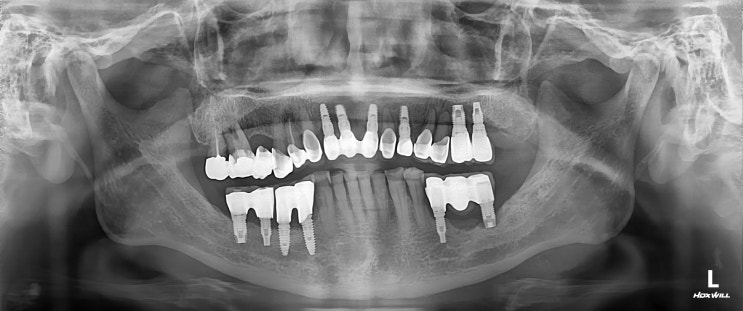

[수서역치과] 망가진 임플란트 재식립

안녕하세요 매서운 한파가 치는 2월입니다 해외나가셨다가 다시 오신 환자분이신데 예전에 진료받은 케이스...